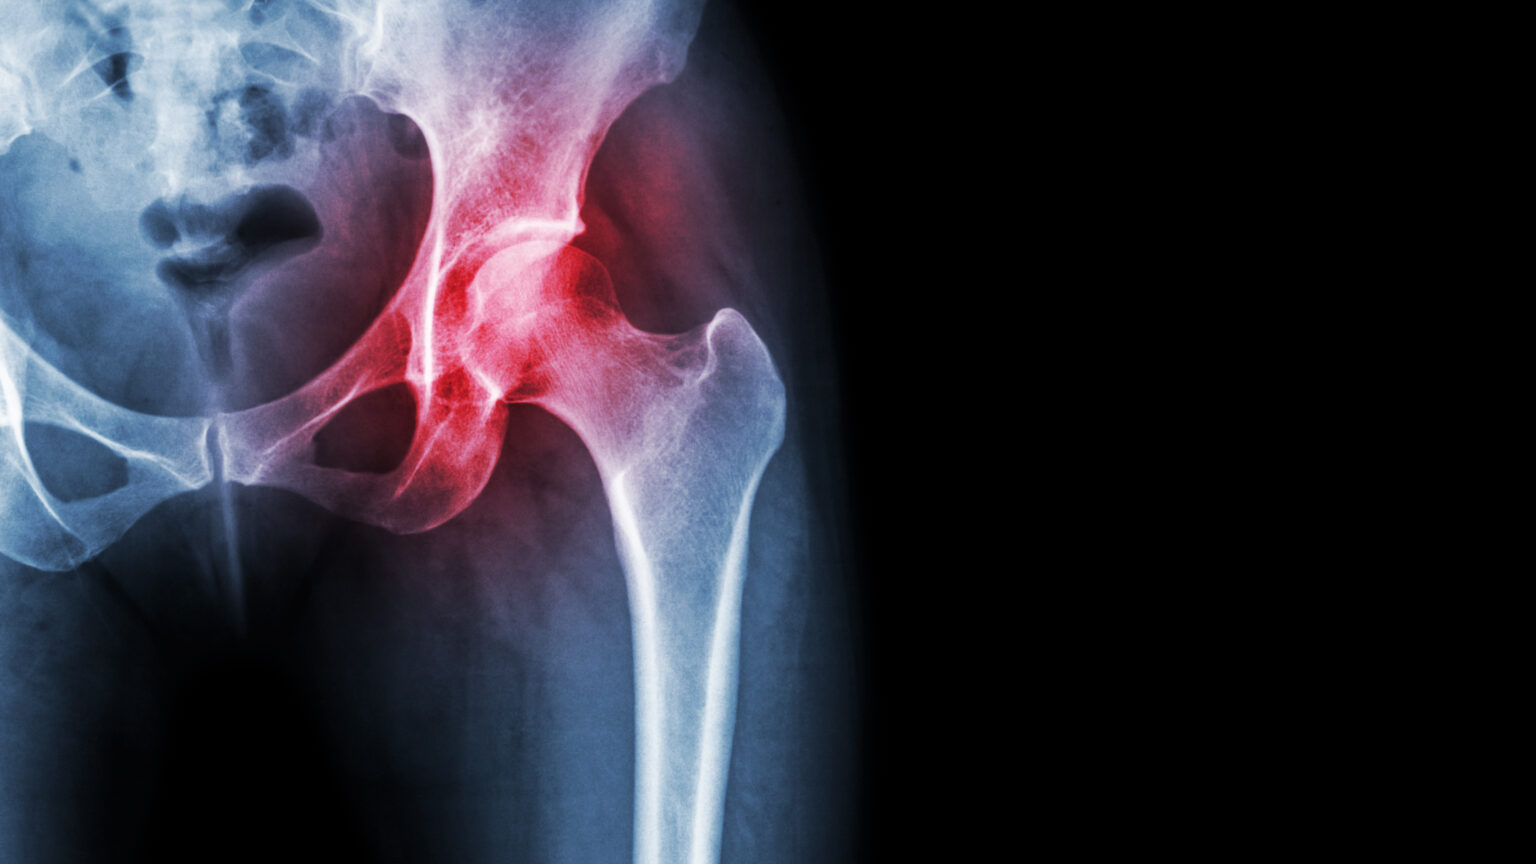

Pain is the #1 reason for joint replacement surgery, but 25% of patients still experience more pain than before surgery

Joint replacement surgery is unnecessary for up to 90% of patients with Osteoarthritis. Despite experiencing significant pain, the majority of patients have mechanically functional and intact joints.

We were frustrated not just by the invasive removal of functioning joints, but also by the large number of patients who have persistent pain after surgery, the extended recovery time and the inherent risks associated with such a major surgery. So, we invested in creating a better treatment because we believe that people deserve better.

Born out of think tank of Physicians, Surgeons, and University Scientists, AROmotion offers a significant advancement in Osteoarthritis care. Surpassing the results of traditional joint replacement surgery, the AROmotion procedure is a minimally invasive treatment that provides patients with both rapid and long-lasting pain-relief.